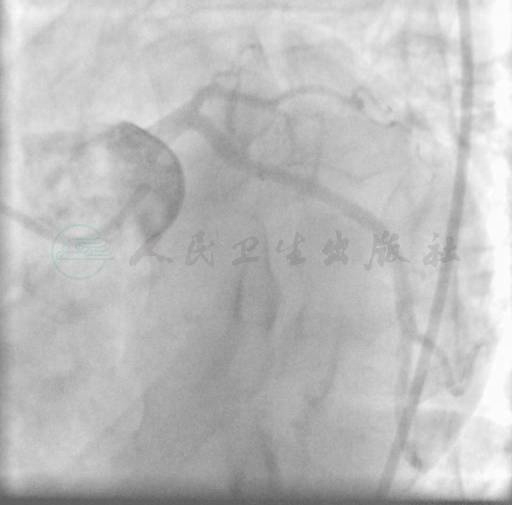

选用右桡动脉径路,6F血管鞘,常规方法行冠状动脉造影。结果显示:右冠状动脉(RCA)中段轻度狭窄性病变(图1),有侧支血管给LAD供血(图2);左主干(LM)无狭窄;左前降支(LAD)7段(高位对角支后)100%闭塞(图3);左回旋支近中段轻度病变,狭窄30%~40%(图4)。

图2 RCA到LAD侧支循环使LAD显影

图3 LAD100%闭塞